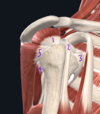

The vessels labeled by #4 most recently originated from which vessel?

Subscapular artery

(Posterior = circumflex scapular artery, anterior = thoracodorsal artery)

Fig. 16.2 Adapted from Gilroy et al. Atlas of Anatomy, second edition, Fig. 24.1B.

Describe the deltoid muscle

- Function:

- Innervation:

- Attachments

Deltoid

- Function: Arm abduction, flexion, internal rotation

- Innervation: Axiliary nerve (C5-C6)

- Attachments: Clavicle, acromion, scapular spine, humerus